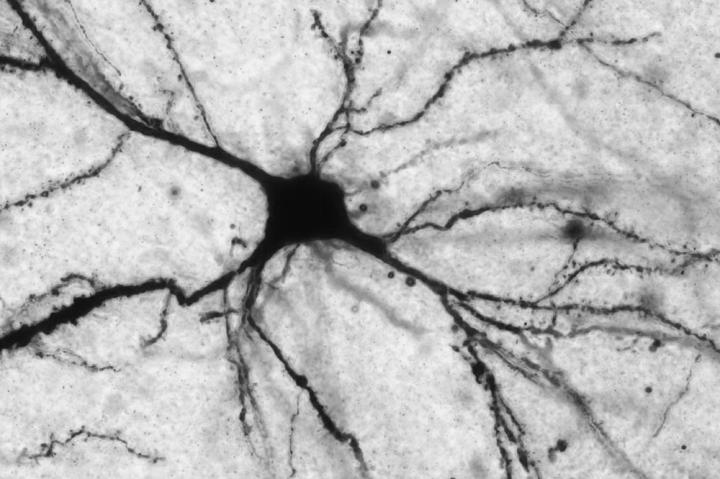

McEwen, the Alfred E. Mirsky Professor, and Nasca, a postdoctoral fellow of the American Foundation for Suicide Prevention, have studied the link between LAC and mood disorders using animal models. In one study, they showed that LAC supplements ameliorate depressive symptoms in mice by reversing brain-cell impairment caused by an excess of glutamate. In a separate rodent study, they observed that LAC treatment reduces depressive behavior and stress-associated neural dysfunction in the medial amygdala, a brain region involved in social interactions. These findings strongly suggest that LAC deficits contribute to a depression-like state in mice, leading the scientists to wonder whether the molecule plays a similar role in humans.